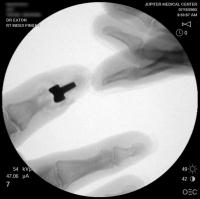

Dorsolateral eponychial splitting incision. The black debris represents foreign body pencil lead debris from a childhood injury.

Intraoperative fluoroscopy.